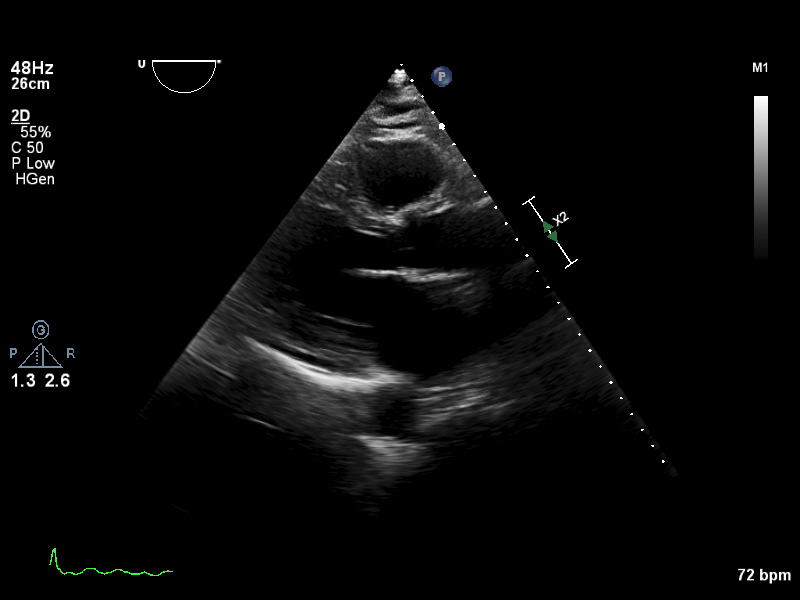

ImageView NameDescription

a4ch-full a4ch-full Apical 4-chamber showing the full depth of all four chambers (no LV/RV focus)